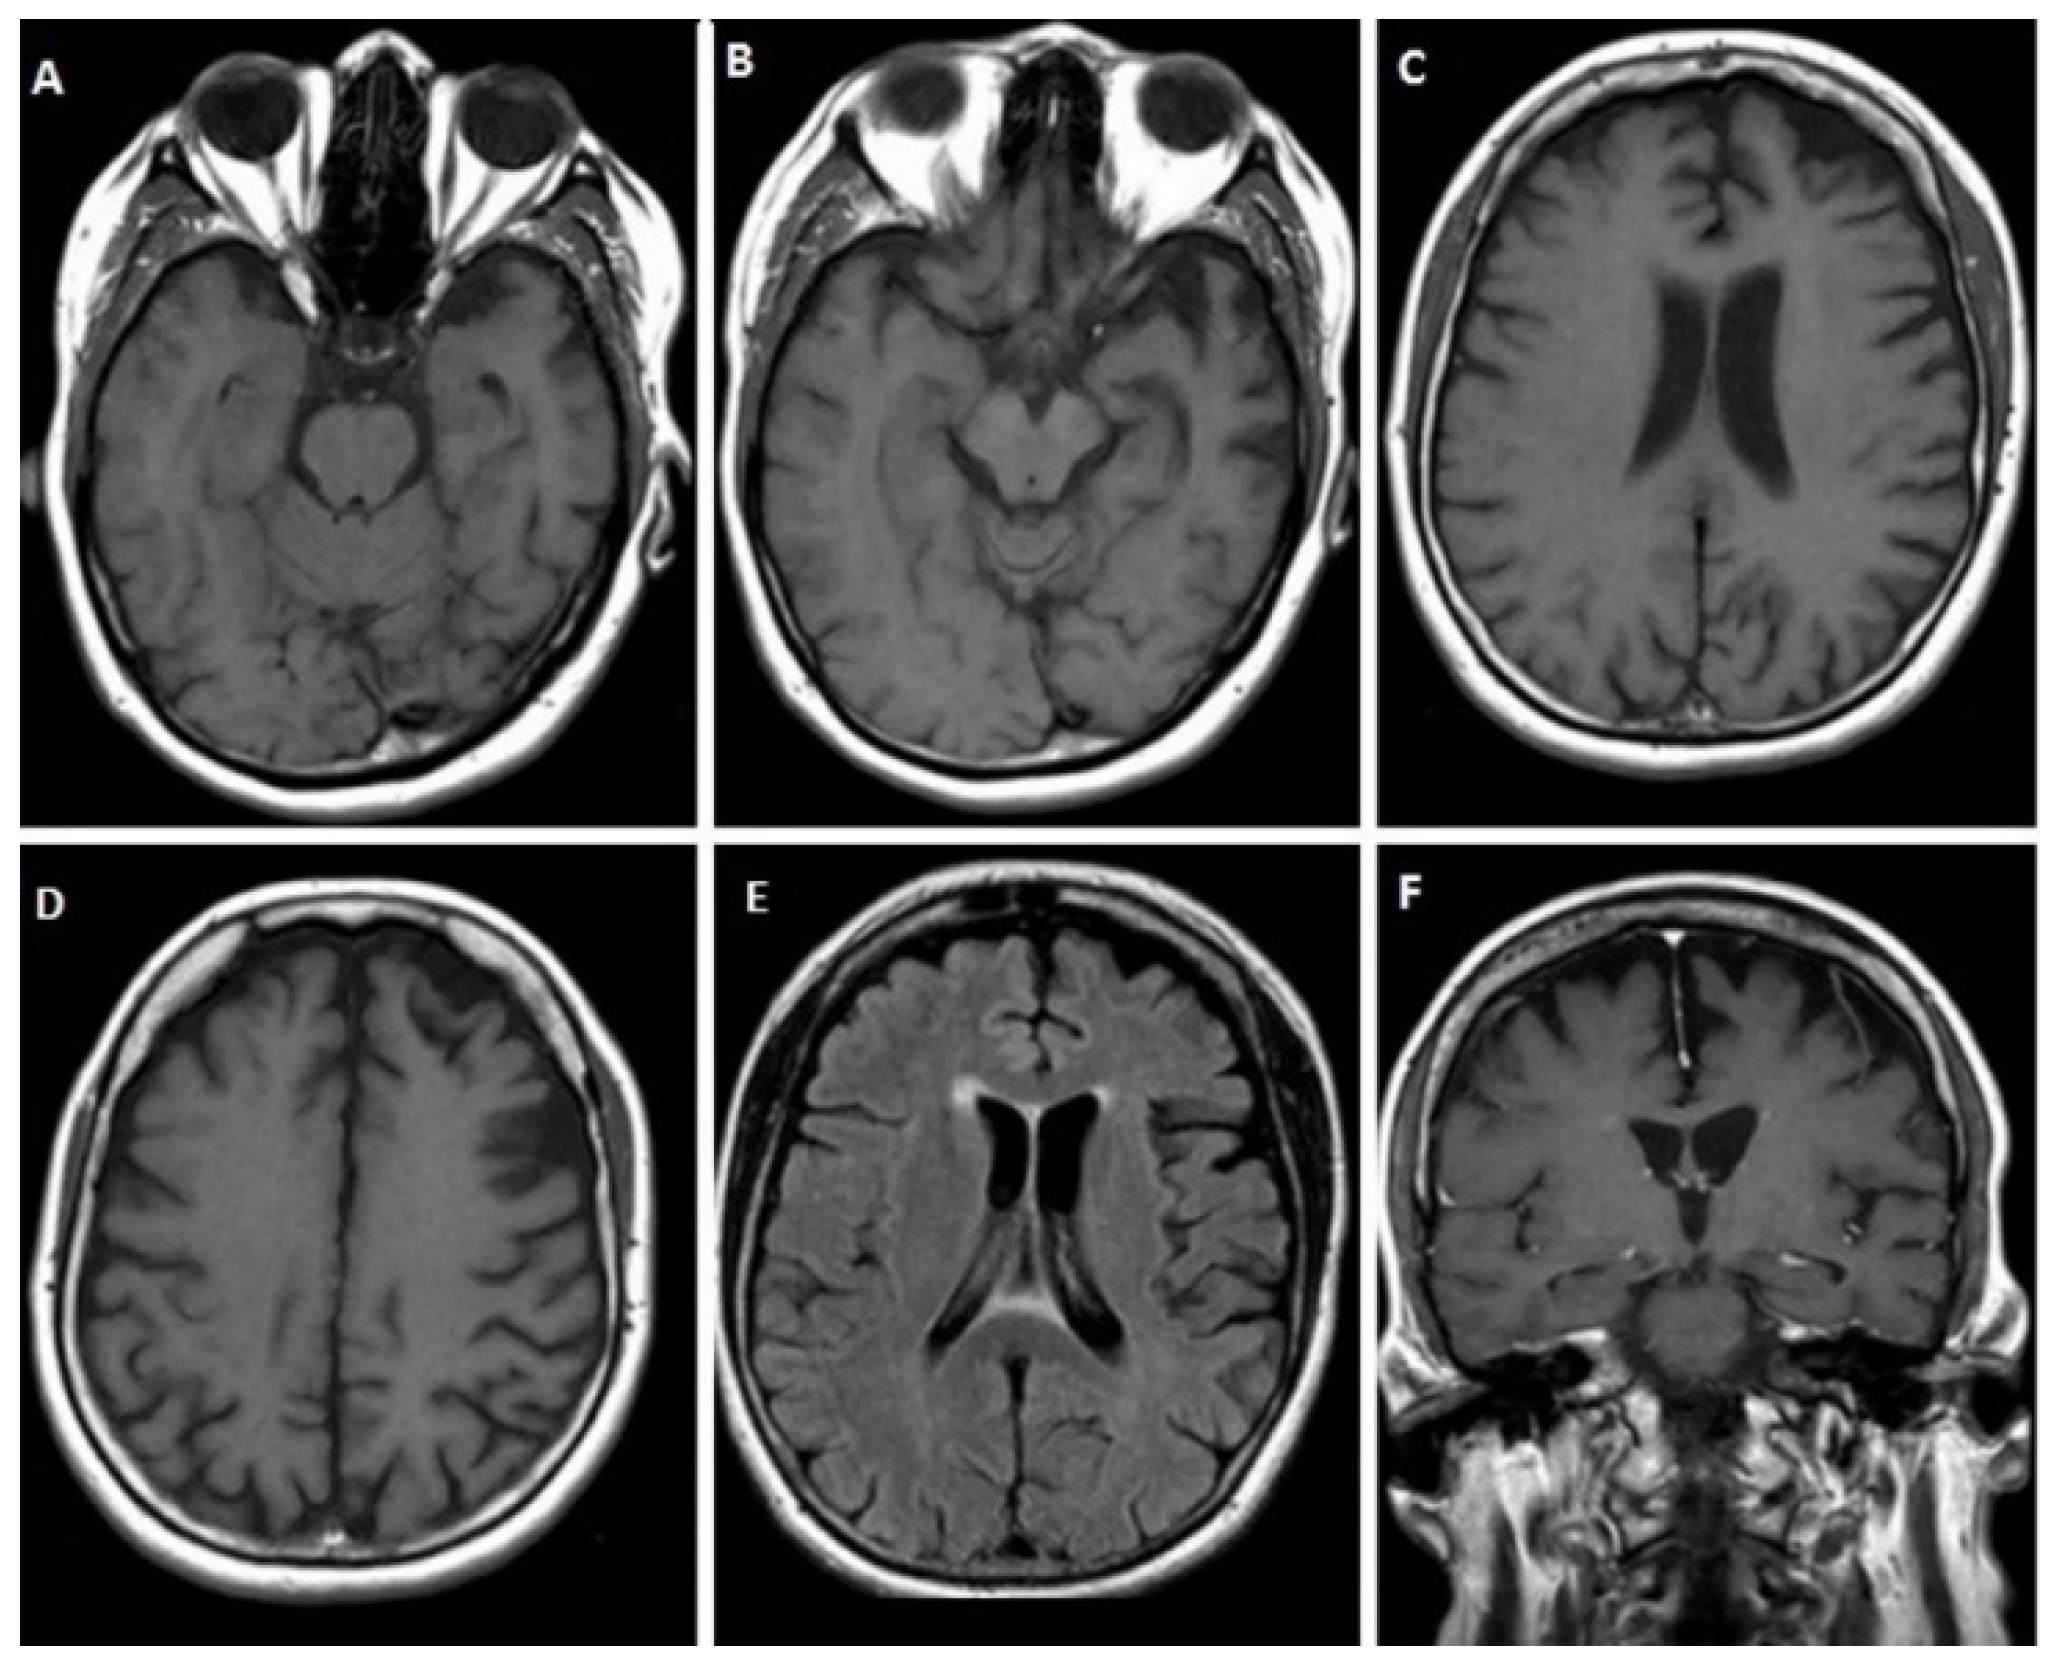

3.1.1. Case 1